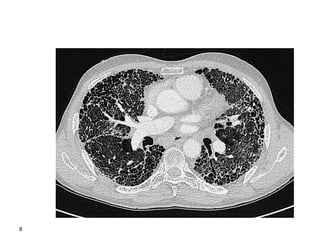

8

9

10

or cryobiopsy Thorax 2008;63(SupplV):v1– v58. doi:10.1136/thx.2008.101691 Diagnostic Algorhithm for ILD cryobiopsy